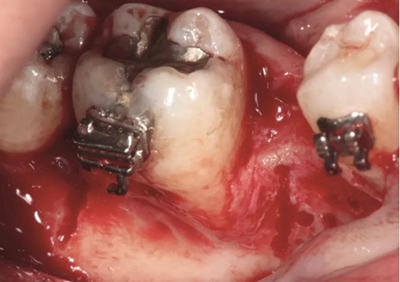

圖2a.病例1中,同期牙槽嵴增量和右下第一磨牙種植位點加速磨牙直立。術(shù)前臨床檢查顯示修復空間小、牙槽嵴吸收

圖2b.增量時,在受區(qū)和右下第二磨牙遠中進行牙槽嵴去皮質(zhì)術(shù)

為患者采用了直絲弓自鎖托槽(Damon,Ormco)。最開始用0.016×0.025 英寸的不銹鋼弓絲(Damon,Ormco)進行矯正和排齊,歷時7 個月。在磨牙直立加力之前,下頜第一磨牙位點無牙區(qū)的近遠中距離為右側(cè)6.5mm、左側(cè)9mm(圖1)。磨牙遠移和直立的目標是實現(xiàn)雙側(cè)最終冠修復體的近遠中直徑達到10mm。右側(cè)第一磨牙位點的大小差異比左側(cè)更大,牙槽嵴吸收更多,頰舌徑約4.5mm(圖2)。在詳細解釋同期牙槽嵴增量和加速磨牙直立程序后,患者選擇右側(cè)位點進行種植治療。因此,為了加速該位點的空間建立,圍繞第二磨牙行選擇性去皮質(zhì)術(shù)和同期牙槽嵴增量術(shù)。

手術(shù)切口位于牙槽嵴頂舌側(cè),溝內(nèi)切口向下頜升支的遠中和頰側(cè)延伸,接著翻全厚粘骨膜瓣。牙槽嵴去皮質(zhì)術(shù)在下頜第一磨牙受區(qū)和第二磨牙牙根遠中進行,用一個高速的碳化鎢鋼球鉆和超聲骨刀進行(Piezosurgery, Mectron)(圖2b)。